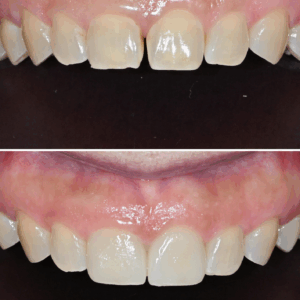

울산삼산동치과 앞니 사이 벌어짐으로 인해 라미네이트로 심미성 회복

울산삼산동치과 앞니 사이 벌어짐으로 인해 라미네이트로 심미성 회복 안녕하세요! 하나치과입니다~:) ​ 예로부터 치아 사이가 벌어지면 그 사이로 복이 달아난다는 속설이 있는데요. ​ 관상학적으로도 벌어진 치아는 복이 새어 나가는 인상으로 인식해 여러모로 좋지 않게 생각해 왔습니다. ​ 치아 사이의 공간을 일컫는 치간 이개의 원인은 선천적, 후천적으로 나눌 수 있는데 벌어진 앞니를 더보기…